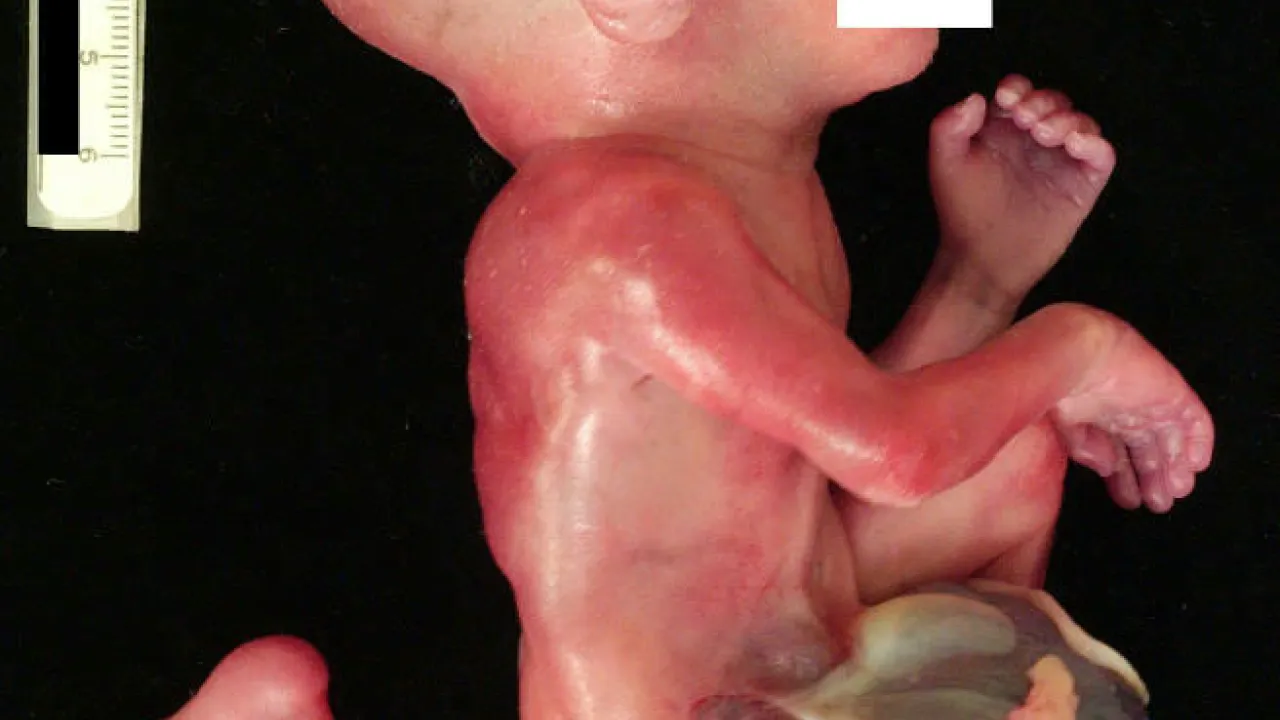

Body Morphology, OEIS Complex